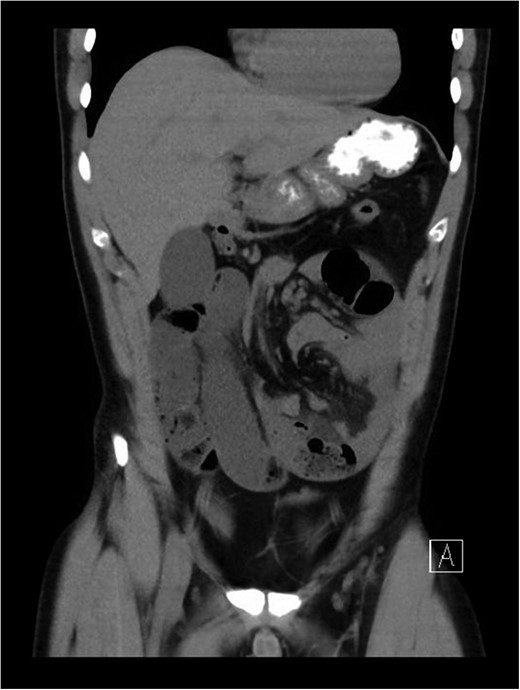

The patient presented to a local hospital at approximately mid-day with worsening severe central abdominal pain associated with vomiting and obstipation. The symptoms had been rapidly progressing over a period of 12 h. He finally presented with pain preventing him from lying flat. Patient had no history of abdominal surgery, trauma or large food bolus. There was no other relevant past personal or family history. On examination, he appeared diaphoretic and in distress, but maintained normal vital signs, except for bradycardia. His examination revealed signs of florid peritonism, with rigid distended abdomen. Initial blood films were only remarkable for hypophosphatemia (0.33 mmol/L) with a normal lactate (1.1 mmol/L) and pH (7.30 with base excess of −3 mmol/L). His white cell count was 11.8 × 109, and had a C-reactive protein of 14. An abdominal computed tomography (CT) scan was performed and revealed features highly suggestive of mid-gut volvulus with associated obstruction and likely vascular compromise (Figs 1 and 2).

Coronal view of CT abdomen and pelvis revealing incarcerated internal hernia with signs of small bowel obstruction, whirl sign suggestive of volvulus.